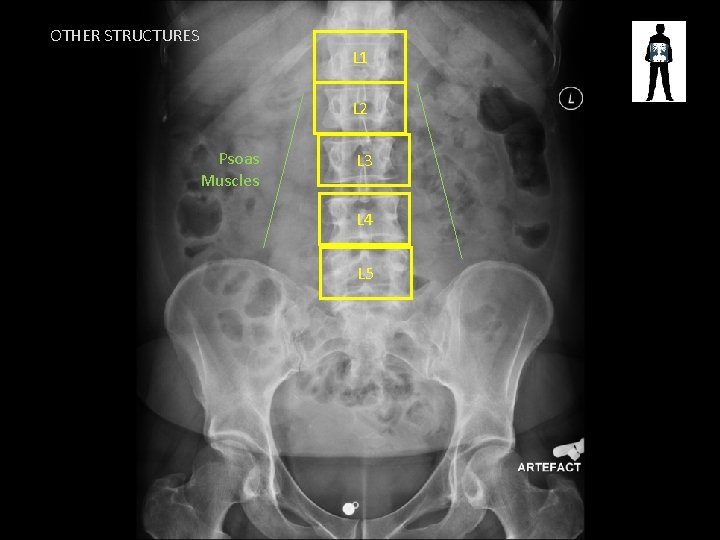

OTHER STRUCTURES L 1 L 2 Psoas Muscles L 3 L 4 L 5